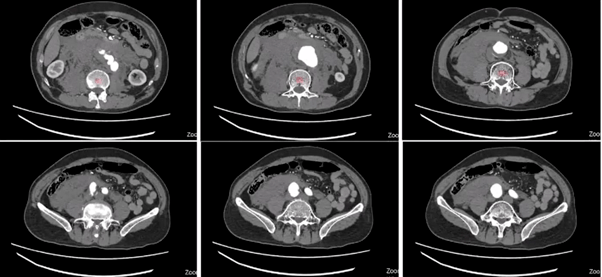

图1-术前ct评估,肾下腹主动脉瘤,右髂内开口狭窄,左髂内动脉开口距离

ct如下 腹主动脉瘤测量数据如下